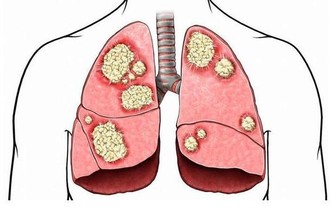

德國一個研究所對此展開了研究,結果發現缺硒會使肝癌的發病率提高10 倍。

該研究團隊大約蒐集了約48 萬名成年人的健康數據,進行了為期10 年的跟踪調查;

經統計,這些調查對像中包括121 名肝癌患者、100 名膽囊癌患者,以及40 名肝內膽管癌患者。

研究人員檢測了癌症患者的血硒水平,並與健康個體的血液樣本進行對比;

而後發現這肝癌患者的血硒水平都遠低於健康人。

與血硒水平較高的人相比,缺硒的個體罹患肝癌的風險要高出5 到10 倍。